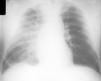

Varón de 69 años de edad diagnosticado 5 años antes de hipertensión arterial que controla adecuadamente con 25 mg diarios de hidroclorotiazida. No refiere otros antecedentes personales o familiares de interés. Acude a la consulta porque desde hace dos semanas refiere cuadro de astenia y disnea con la actividad física habitual. No refiere disnea en reposo, dolor torácico o palpitaciones. En la exploración física la tensión arterial sistólica es de 150 mmHg y la diastólica de 90 mmHg. La presión venosa yugular es normal (2,5 cm por encima del ángulo de Louis). La auscultación cardíaca es rítmica a 44 latidos por minuto (lpm) con algún extratono. No se auscultan soplos. La auscultación pulmonar muestra estertores finos en ambas bases pulmonares. La palpación del abdomen es normal. No presenta edemas en las extremidades inferiores. Se realizó un electrocardiograma (fig. 1) que muestra un ritmo sinusal de base a 75 lpm con un bloqueo AV; de segundo grado; en parte del trazado el bloqueo es 2:1 y en otros es un bloqueo AV de segundo grado tipo Wenckebach. La radiografía de tórax (fig. 2) muestra una silueta cardíaca normal con un índice cardio-torácico (ICT) normal. Existe un infiltrado intersticial predominante en hemitórax derecho, con visualización de la cisura menor y pinzamiento del seno costofrénico derecho compatible todo ello con insuficiencia cardíaca. Con el diagnóstico de insuficiencia cardíaca y bloqueo AV de segundo grado el paciente fue remitido al Servicio de Urgencias del hospital, donde ingresa. Se realizó un hemograma, bioquímica sanguínea y un ecocardiograma que fueron normales. En la monitorización continua se puso de manifiesto que presentaba bloqueo AV alternando bloqueo AV de segundo grado 2:1 y Wenckebach, como en nuestro electrocardiograma y fases de bloqueo AV más avanzado Mobitz II. Finalmente se implantó un marcapaso definitivo.

Figura 2. Radiografía de tórax en la que se observa silueta cardíaca normal con un ICT conservado. Existe un infiltrado intersticial predominante en hemitórax derecho, con visualización de la cisura menor y pinzamiento del seno costofrénico derecho.